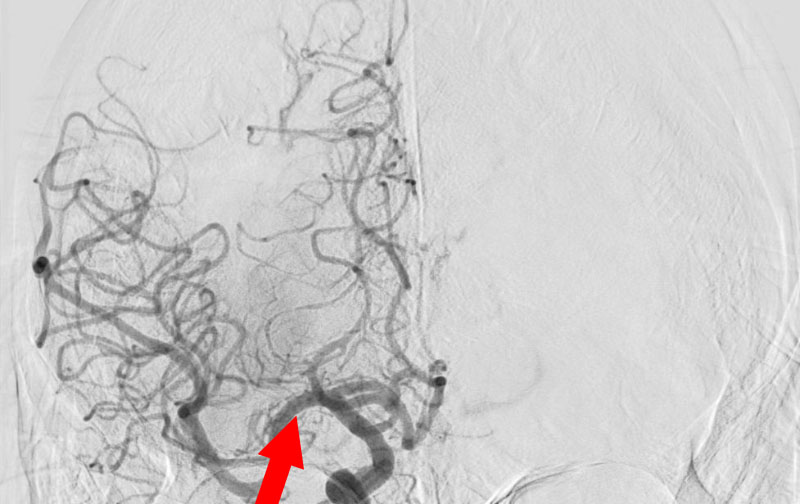

1607

'26年1月8日

脳梗塞・急性期

70代

救急外来

'26年1月